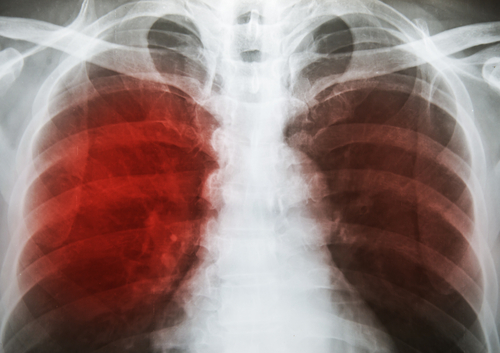

In Mumbai, TB deaths spark data dispute between BMC, NGO

The assessment released two weeks back, was based on data accessed through Right to Information (RTI) filings from the BMC, which refutes its conclusions saying the data has been put together "unscientifically".Praja Foundation alleges that the BMC switched to a new software in December 2015, whose design prevents it from accessing its own data on mortality, leaving it with no way of knowing if Praja Foundation's estimate is incorrect.In its The State of Health of Mumbai report, Praja Foundation assessed that 6,472 Mumbaikars died of TB during 2016-17 -- nearly 18 people every day. It showed a 37 per cent increase in the number of TB cases in Mumbai -- from 36,417 in 2012-13 to 50,001 in 2016-2017.Data for the report were compiled through RTI filings with municipal and government hospitals and dispensaries.Data on the cause of death were not available from December 2015 onwards. Praja, working in collaboration with data analytics company Hansa Cequity Solutions, extrapolated the cause of death from January 2016 to March 2017 using a predictive model that Praja Foundation claims gives "the closest possible accuracy of up to 95.5 per cent".

The number of TB cases treated through DOTS, the standard treatment programme for TB, has fallen by 50 per cent over four years -- from 30,828 in 2012 to 15,767 in 2016.Simultaneously, the percentage of defaulters -- patients whose TB treatment was interrupted for more than two months -- in DOTS centres has increased from nine per cent in 2012 to 19 per cent in 2016, even as the government has been promoting its "TB haarega, desh jeetega" (TB will lose, India will win) campaign.A ward-wise compilation of the number of TB cases shows that from 2012-13 to 2016-17, TB incidence was highest in L ward (Kurla), which had 1,254 patients.The report also reveals a discrepancy in the number of TB deaths reported by different sources. The Tuberculosis Control Unit of the BMC reported 1,459 deaths in 2015, while the Public Health Department issued 5,680 death certificates in which the cause of death was recorded as TB across 24 wards in 2016.